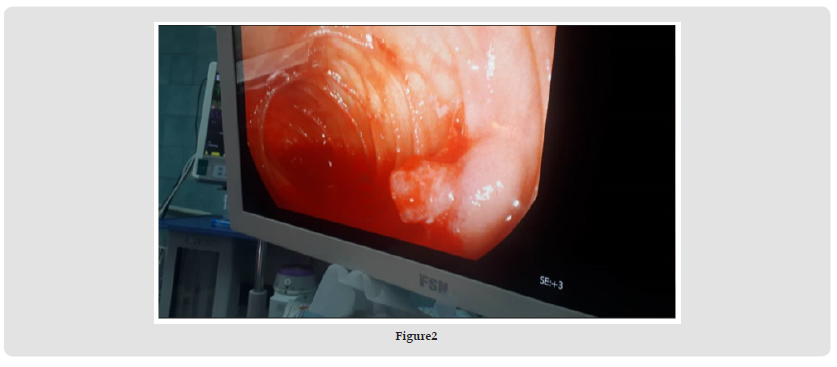

After aggressive endoscopic irrigation of fresh blood and blood clots with normal saline fluid, we found a mucosal protruding vascular lesion (approximately 0/5 cm in diameter), with pulsatile spurting bleeding at distal jejunum approximately 160cm from the Triet’z ligament. A single external suture as a mark was placed over the lesion by the surgical team and flexible endoscope was carefully removed. Then a small incision enterotomy was performed on jejunum just near the mark and suture-ligation of lesion with complete hemostasis was done. for both incision Entroraphy was performed. Patient received two units of packed red blood cells, platelets and FPP during operation. Patient’s vital signs became stabilized after operation; his hemoglobin and platelet values rose to 11.1 mg/dL and 172,000/mm after transfusion of four units of packed red blood cells and four units of FFP. Patient started a fluid diet four days after surgery and discharged six days after the operation. There was no recurrence of bleeding in the follow-up period.

Endoscopic management is the first line of therapeutic intervention, and to reach distal locations, either single or double balloon-assisted enteroscopy can be instrumental. Regional injection with epinephrine (dilution, 1:10 000) is a popular, inexpensive treatment modality, but it carries a high rate of rebleeding if used alone and hence is always coupled with another intervention [8-10]. Injecting sclerosants like ethanol or polidocanol has been successfully used to achieve hemostasis in a few previous case reports [9,11]. Thermal coagulation using contact (bipolar or monopolar probes) or noncontact (argon plasma coagulation) techniques or mechanical interventions include placing hemoclips, over-the-scope clips, or banding can also be performed [12-14]. However, in our case, these options was not done because the patient was clinically unstable. According to Diagnostic and management algorithm for obscure gastrointestinal bleeding, hemodynamically unstable patients with major bleeding must prepare for operating room and localizing source of bleeding is done by intraoperative entroscopy or intestine serial clamping technique [15]. The endoscopic-surgical combined cases report in the literature described DLs that are identified through endoscopy and then subsequently resected [16] (Figures 1 & 2).

We adapted a multidisciplinary approach by intraoperative enteroscopy in coordination with the surgical team who suture-ligate the bleeding lesion from the intraluminal aspect by minimal enterotomy near side the lesion. This case is unique not only regarding the unusual location of the lesion but also regarding the multidisciplinary approach necessitated for the management of this catastrophic hemorrhage that avoided surgical resection. According to our knowledge, this the first report of mid-jejunal Dieulafoy’s lesion that managed by suture- ligation without any resection.